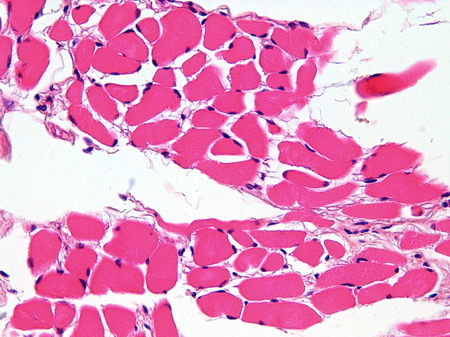

| IB-6 Lengua (Hematoxilina-eosina) |

Visión general: sección de lengua vista a pequeños aumentos y teñida con hematoxilina férrica que nos permite ver muy bien la ubicación de las fibras musculares lisas por debajo de la capa mucosa. Se observan haces de fibras musculares estriadas esqueléticas dispuestos en todas las direcciones del espacio.

Visión específica: a mayores aumentos (10X) y ahora ya teñido con hematoxilina-eosina podemos observar paquetes de fibras musculares estriadas esqueléticas entremezcladas con adipocitos. Obsérvese el carácter cilíndrico de las células y la presencia de múltiples núcleos localizados en la periferia de las mismas. Los grandes aumentos (40X) nos permiten visualizar a la fibra muscular estriada esquelética tanto en sección longitudinal como transversal. En ambos casos observamos los núcleos en la periferia de la célula, mientras que la sección longitudinal permite observar la estriación típica de banda oscura banda clara.